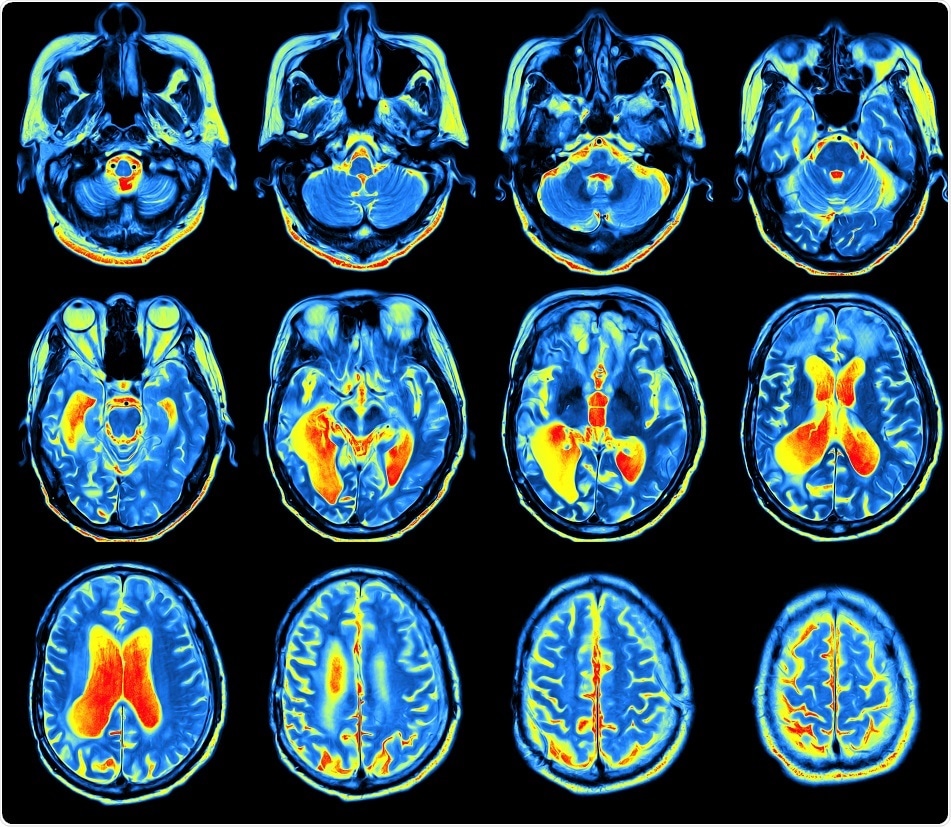

Credit: MriMan/ Shutterstock.com

The study, which was published in the journal Neuron, suggests that it is possible to build up a map of the connectome---the connections in the brain---by examining conventional brain scans obtained using a magnetic resonance imaging (MRI) scanner.

The current study used a conventional 3T MRI scanner---where 3T stands for the strength of the magnetic field---to compare the brains of 296 typically developing adolescent participants. The findings were then validated via a cohort study of another 124 participants.

A conventional MRI scan provides a single image of the brain that enables the calculation of multiple structural features of the brain; i. e., each region of the brain can be described using nearly ten distinct characteristics.